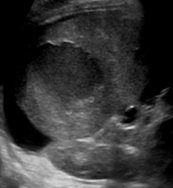

Identify this image.

Subscapular hematoma

What is an intraparenchymal hematoma?

Blood collection within parenchyma

intraparenchymal hematoma